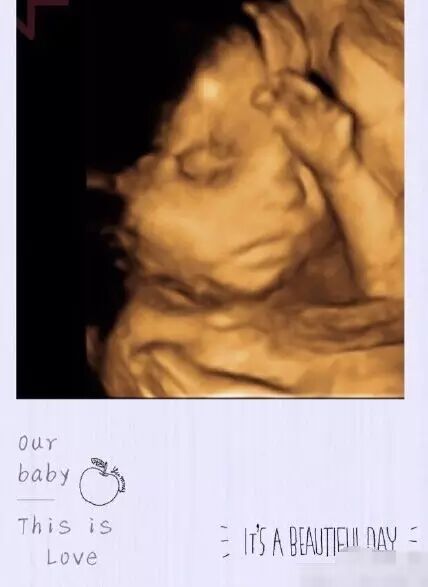

晒胎宝宝

宝宝到来的过程总是焦急又兴奋,在他降临世界之前,是否千万次幻想宝宝的样子,每次翻身,每个表情,四维彩超都可以给您最真实的呈现,留下一份很好的纪念。

常德丽人妇产医院独家引进韩国麦迪逊

韩国麦迪逊四维彩超是四维彩超技术的发明者,与普通四维彩超相比,在图像质量、探头技术等上实现突破,提供更多、更精准的图像数据,进一步助力精准诊断及早期疾病检查,传递全方位的母婴关爱。